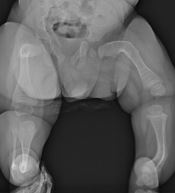

Osteogenesis Imperfecta (OI)

OI otherwise known as ‘brittle bone disease’ is a condition in which bones and other tissues in the body are weak due to defect in the collagen protein. Because of this, bones are unable to withstand mechanical forces and they break easily.